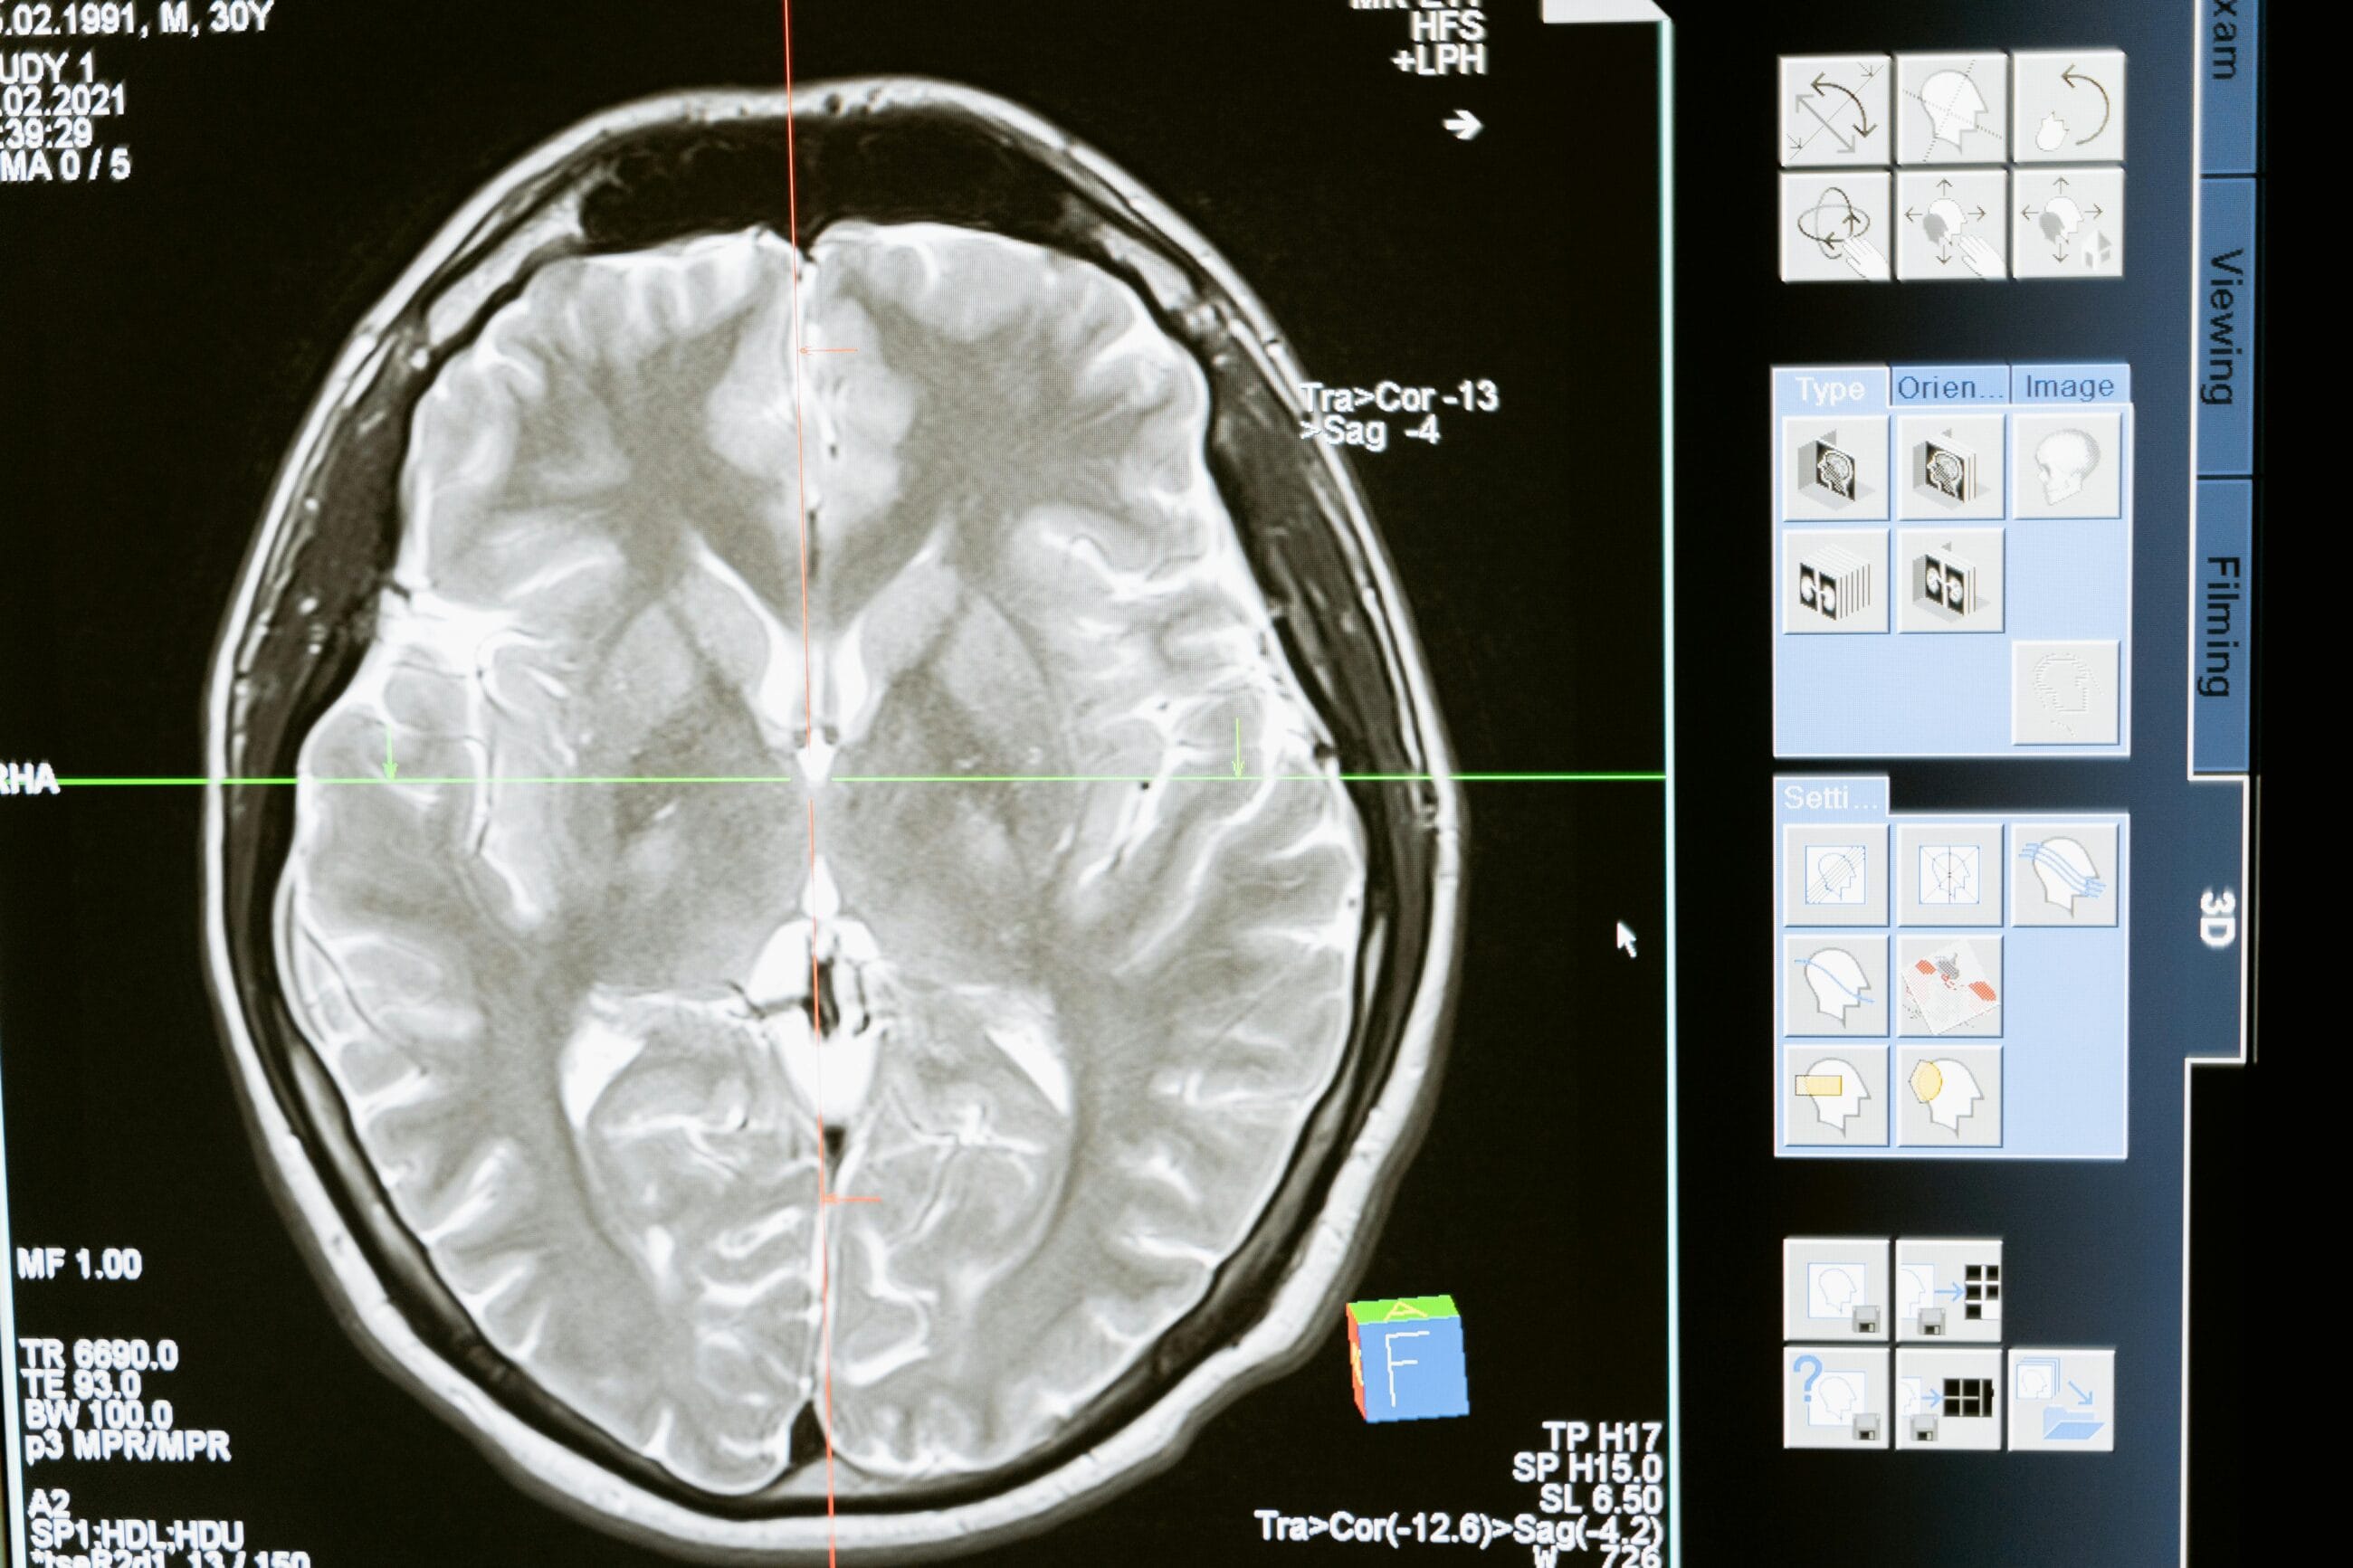

Low-Dose CT for Lung Cancer

What it is: A specialized CT scan used to screen for lung cancer in high-risk individuals, such as smokers.

Who it’s for: Current and former heavy smokers aged 50-80.

Why it matters: Early detection of lung cancer can more than double survival rates.

- AI-Driven Diagnostics that analyze imaging results faster and more accurately.